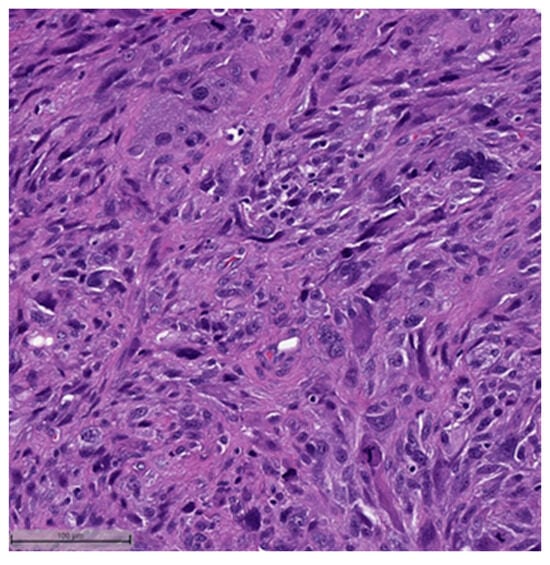

Figure 2. Squamous cell carcinoma component (H&E, 20×).- Spindle cell carcinoma (SpCC) (Figure 3);

Figure 3. Spindle cell carcinoma (H&E, 20×). - Metaplastic carcinoma with heterologous mesenchymal differentiation (MCHMD);

This system is primarily based on the specific metaplastic elements present within the tumors, while also highlighting the potential overlap that can exist between various histological subtypes [6]. Consequently, numerous cases diagnosed as MpBCs, are accompanied by a detailed description of the histological component or a combination of different component types and/or differentiations. The following figures illustrates a few examples: spindle cell carcinoma component with pleomorphic features (Figure 4), metaplastic breast carcinoma with chondroid differentiation (Figure 5), metaplastic breast carcinoma with a matrix-producing component (Figure 6), metaplastic breast carcinoma with osseous differentiation (Figure 7), and extensive trabeculae bone and hematopoietic tissue (Figure 8).

Figure 5.

Metaplastic breast carcinoma with chondroid differentiation (H&E, 20×).